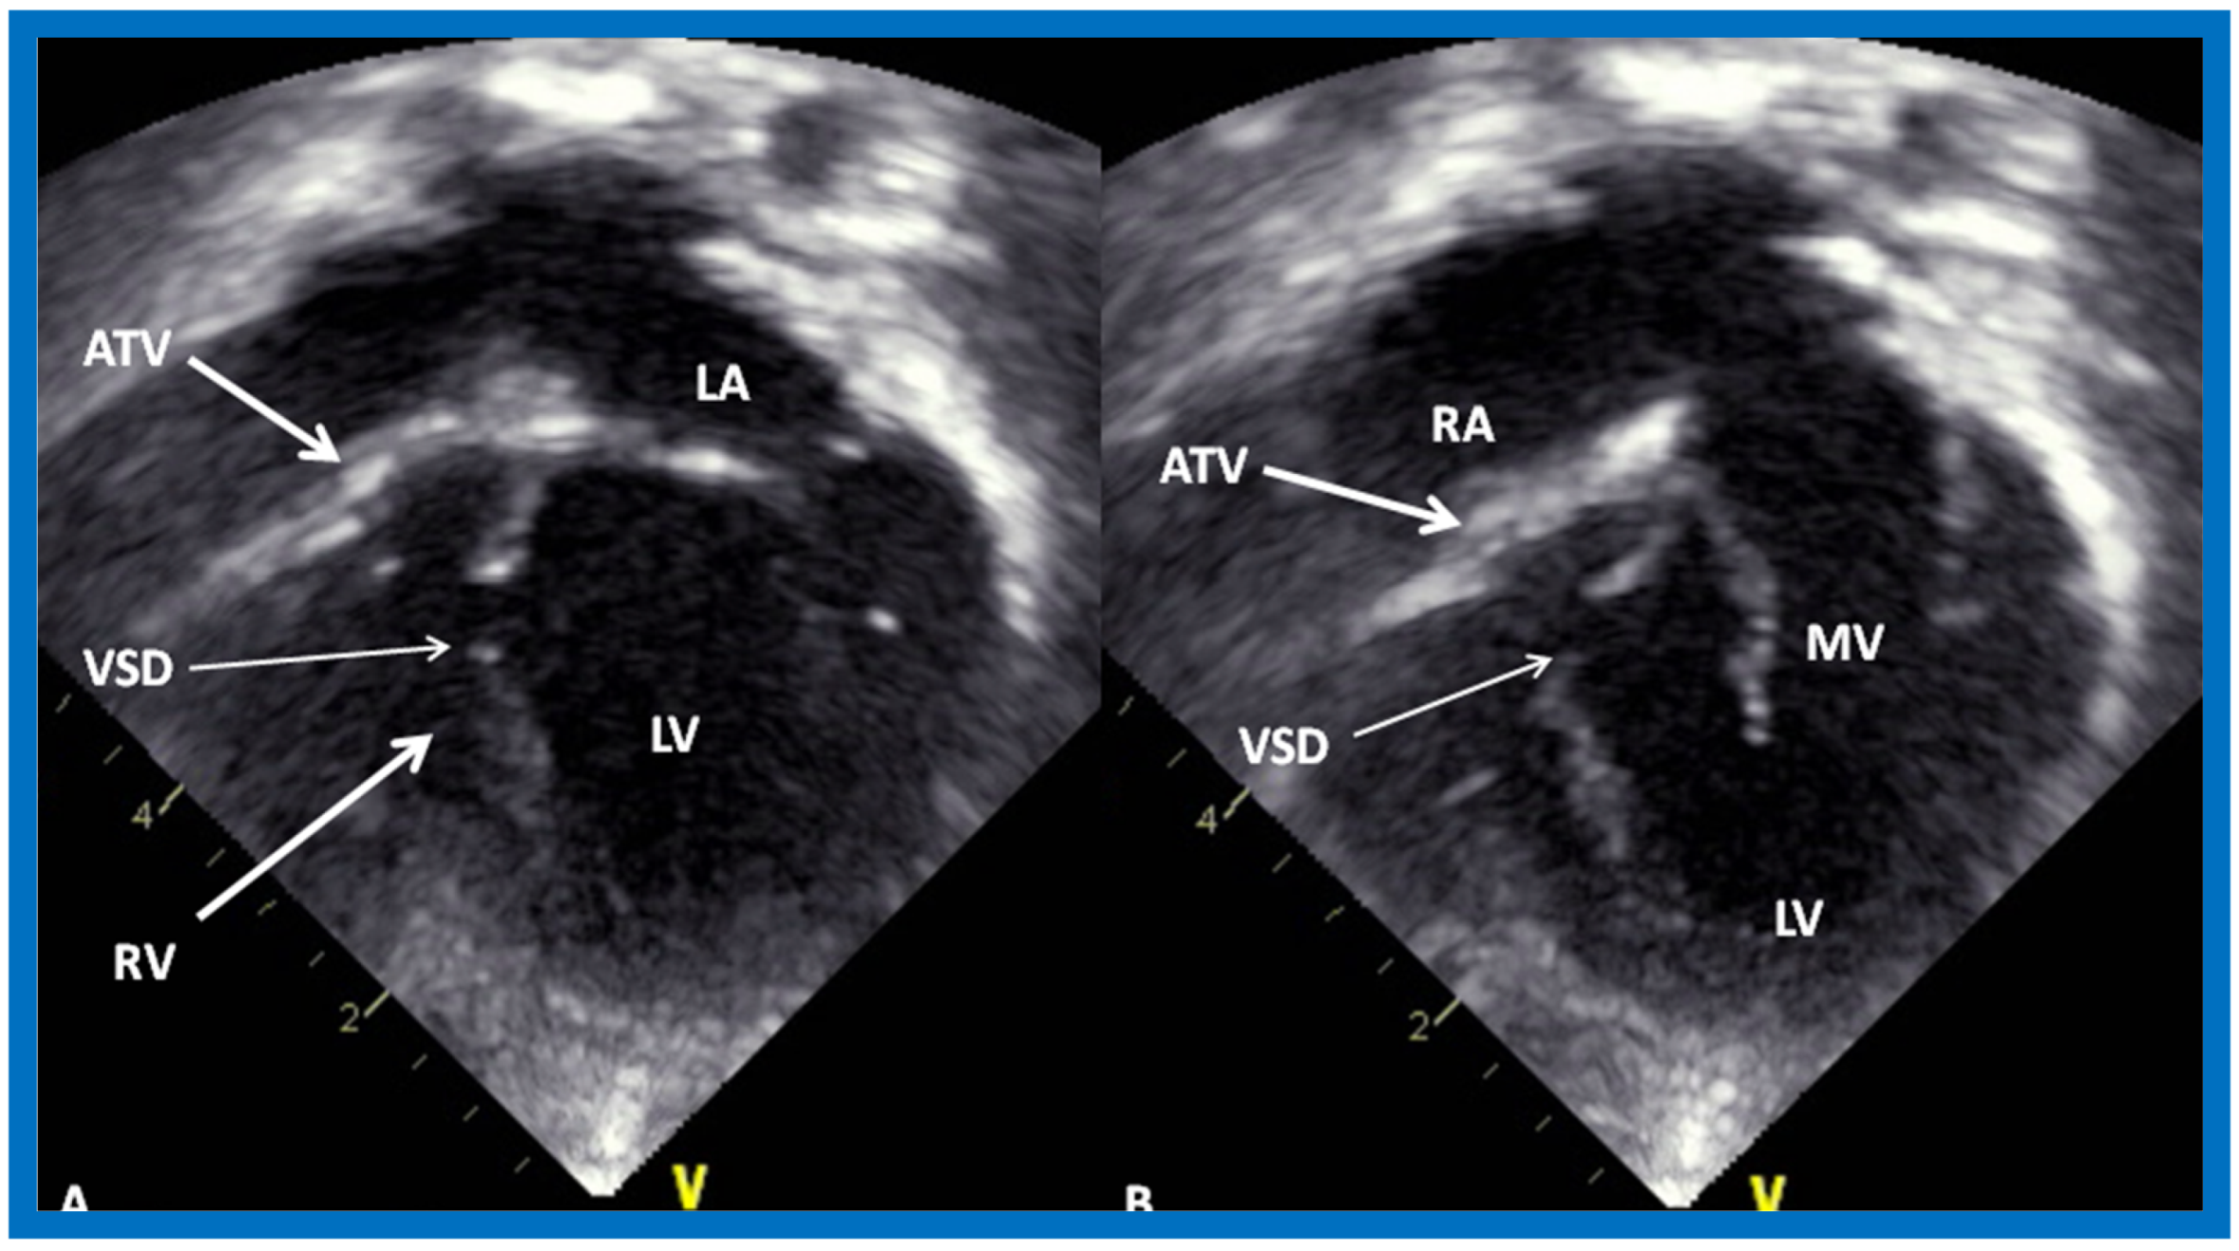

Figure 15.

Selected video frames from subcostal four-chamber view of a two-dimensional (2-D) echocardiographic study demonstrating atretic tricuspid valve (ATV) (thick arrow), represented by a dense band of echoes between the right atrium (RA) and hypoplastic right ventricle (RV). In (A), the mitral valve (MV) is closed, while in (B), it is open. Note the improvement from the pictures shown in Figure 14. LA, left atrium; LV, left ventricle. Reproduced from Rao P.S. [35].

More recently, the author reviewed the echo-Doppler evaluation of tricuspid atresia [37,38,39]; these findings will be presented. M-mode echocardiography, while not diagnostic, is useful for evaluating the size of the left atrium (LA) and left ventricle (LV) and LV function. On 2D echocardiography, the atretic tricuspid valve is visualized directly as a dense band of echoes at the site where the tricuspid valve should be in the most frequent muscular type, as shown in Figure 14, Figure 15, Figure 16 and Figure 17. This anatomy is better demonstrated in apical and subcostal four-chamber views than in other views. The other types, namely membranous, valvular, Ebstein’s, atrioventricular septal and unguarded valve with muscular shelf (Figure 18) [40], are rare and may also be recognized on 2D echocardiography.

Selected video frames from apical four-chamber, 2-dimensional echocardiographic views of a neonate with tricuspid atresia showing an enlarged left ventricle (LV), a small right ventricle (RV) and a dense band of echoes at the site where the tricuspid valve echo should be (ATV) (thick arrow) with closed (A) and open (B) mitral valve. A moderate sized ventricular septal defect (VSD) (thin arrows) is shown. LA, Left atrium; RA, Right atrium. Reproduced from Rao P.S. [39].